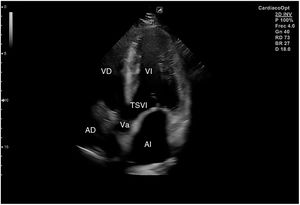

Para obtener los planos apicales la sonda se coloca sobre el latido cardiaco en el ápex, bajo la mamilla izquierda, a la altura del quinto espacio intercostal, con la marca dirigida a la izquierda del paciente y angulado en dirección al hombro derecho. Este plano, apical de 4 cámaras (fig. 8), muestra las 4 cavidades cardiacas y las válvulas auriculoventriculares vistas desde el ápex (fig. 9). En él, el plano del anillo tricuspídeo se sitúa más cerca del ápex que el mitral y el VD se ve más trabeculado. Es la vista de elección para medir la superficie de la AI, comparar el tamaño de ambos ventrículos y descartar la presencia de disfunción y/o dilatación ventricular. Angulando el transductor hacia anterior se obtiene el plano apical de 5 cámaras, que permite observar el tracto de salida del VI y valorar el flujo a través de la válvula aórtica (fig. 10); y al rotarlo 90° en sentido antihorario, el apical de 2 cámaras, que muestra las paredes anterior e inferior del VI (fig. 11).

Para obtener el plano subcostal, con el paciente en decúbito supino, se orienta la sonda desde el epigastrio hacia el hombro izquierdo, con una inclinación de unos 15°, utilizando el hígado como ventana acústica. Esta es una ventana muy útil en pacientes con enfermedad pulmonar. En este corte (fig. 12) aparecen las 4 cámaras separadas por sus correspondientes septos; el VD es el más próximo al transductor, por lo que aparece en la parte más superior y próxima en la pantalla.